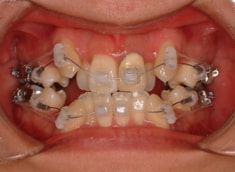

治療開始時

治療開始から約1年後

骨格的な下顎前突の傾向は強くはありませんが、歯牙の状態によって反対咬合が認められます。LowTongue(低位舌)もあります。

修復歯、補綴歯もあります。下顎8番が水平埋伏しています。